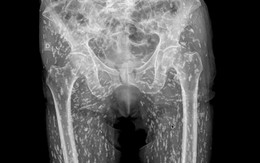

Xem ảnh chụp X-quang thấy hông bệnh nhân chi chít đốm trắng, bác sĩ nói không nên ăn loại thịt lợn này

Sống khỏe 2025-01-26T07:12:00Bác sĩ Sam Ghali ở Mỹ đã phải thốt lên “Đây là kết quả chụp X-quang điên rồ nhất mà tôi từng thấy” khi khám cho một bệnh nhân nam.